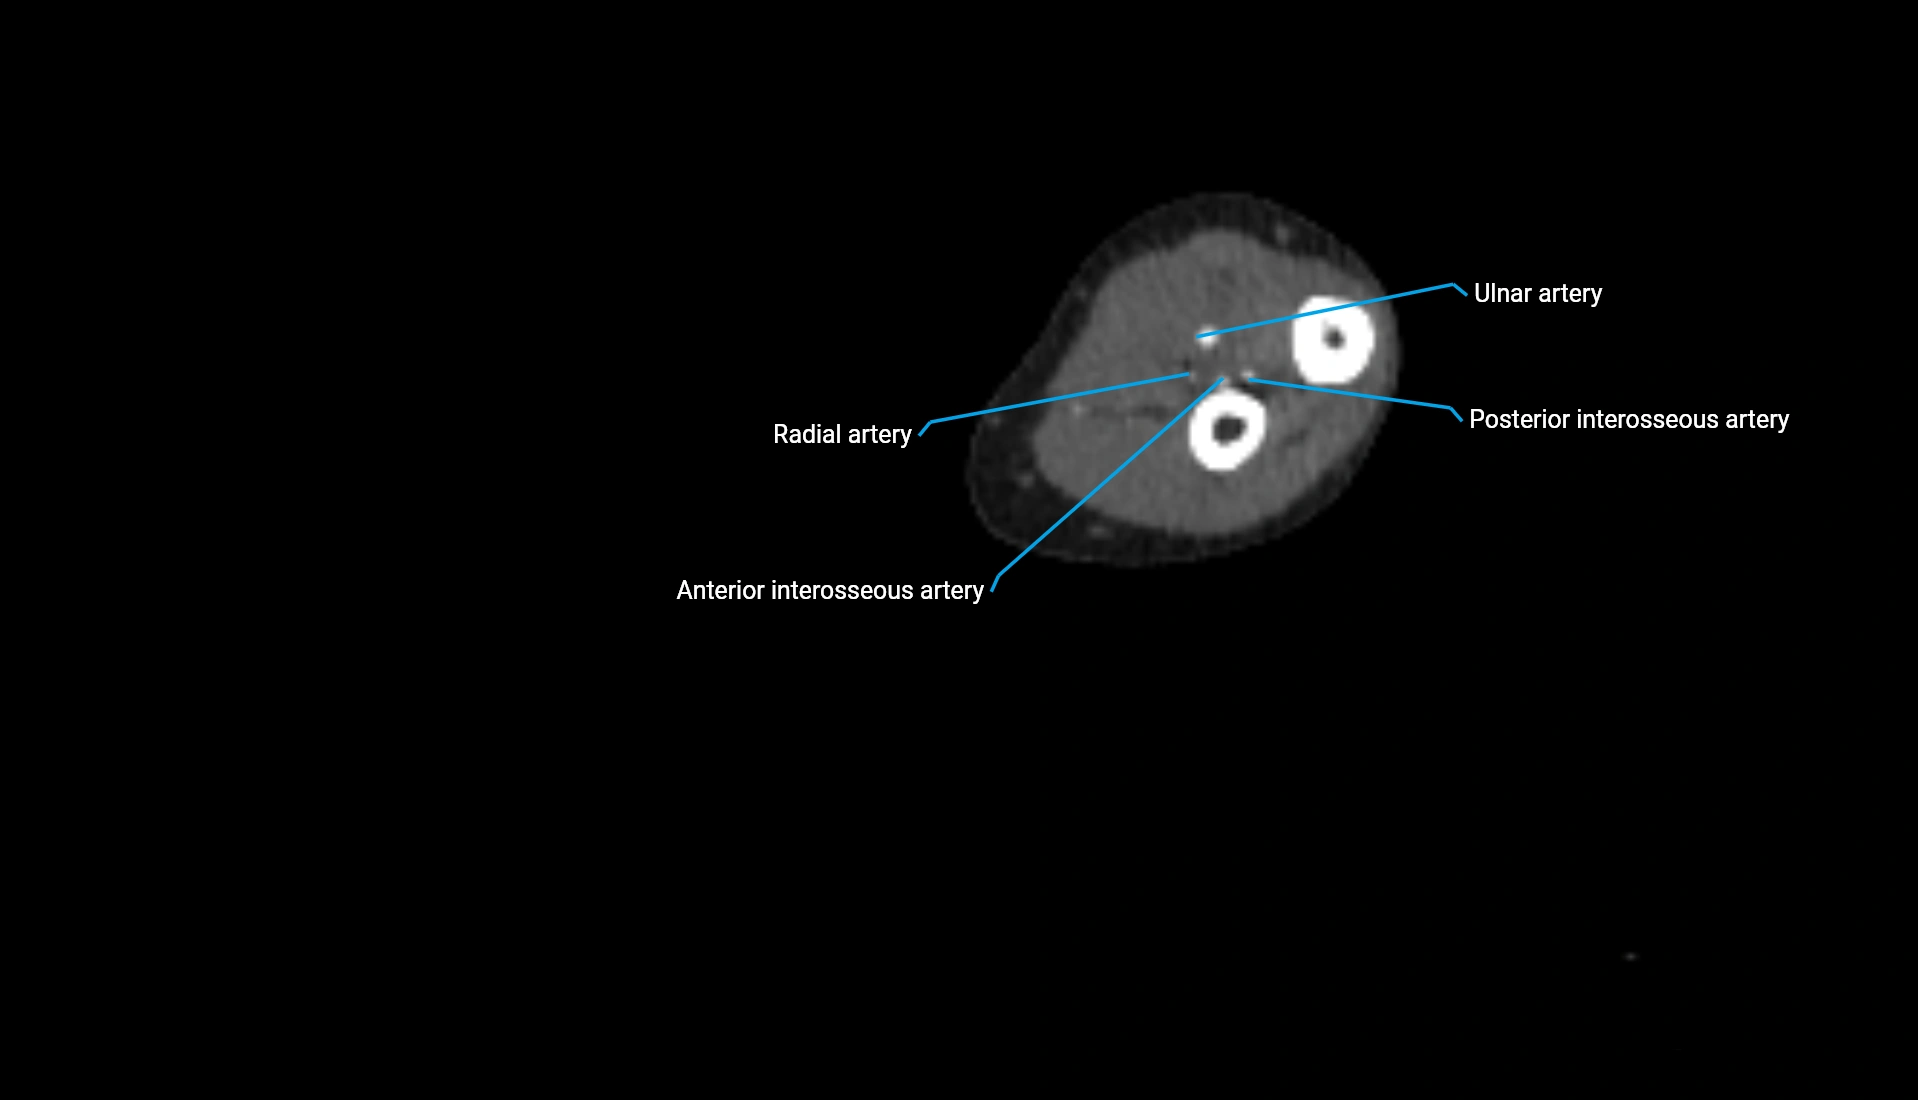

CT Appearance

Non-Contrast CT:

• Cortex: High-density, sharply defined

• Subchondral bone: Dense cancellous matrix

• Articular surface: Smooth concave contour articulating with the capitellum

• Excellent for evaluating bone integrity, alignment, and subtle fractures